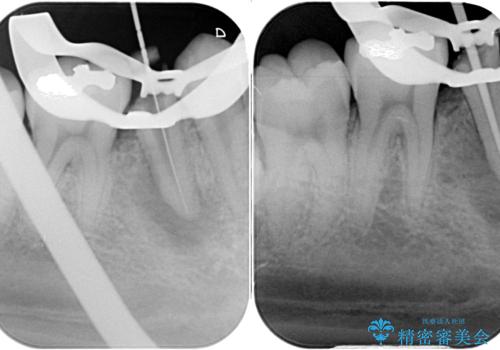

以前通われて医院にて、再度根管治療が必要であると伝えられていたようですが、レントゲン写真などの診察を行った結果、再根管治療が必要な状態でした。

レントゲン写真より、当該歯周囲に大きな透過像があり、歯槽骨が炎症により吸収している様子が認められます。

痛みが続く場合には、次の一手として歯根端切除術にて対応することを説明した上で治療を開始しました。

根管治療後9ヶ月で撮影したレントゲン写真より、歯根周辺の透過像が十分に消失している様子が認められました。